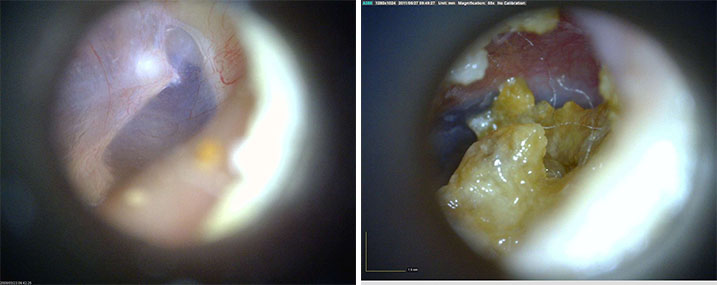

AF4113-EUT

產品參數(shù)

效果展示